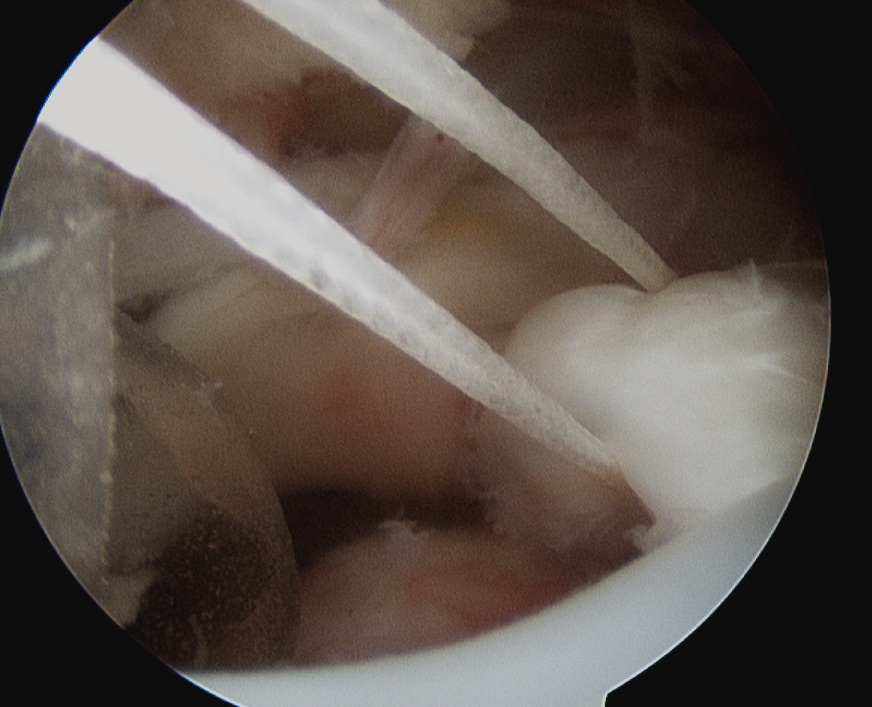

GHJ

- identify tendon

- work through portal Wilmington

- grasp, forms comma sign

- tag SSC with fibrewire